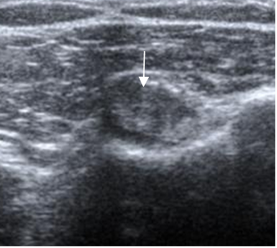

Fig 149. Tendinitis crónica de la cabeza larga del bíceps.

Ecografía coronal. Engrosamiento de la cabeza larga del biceps, por tendinitis crónica.